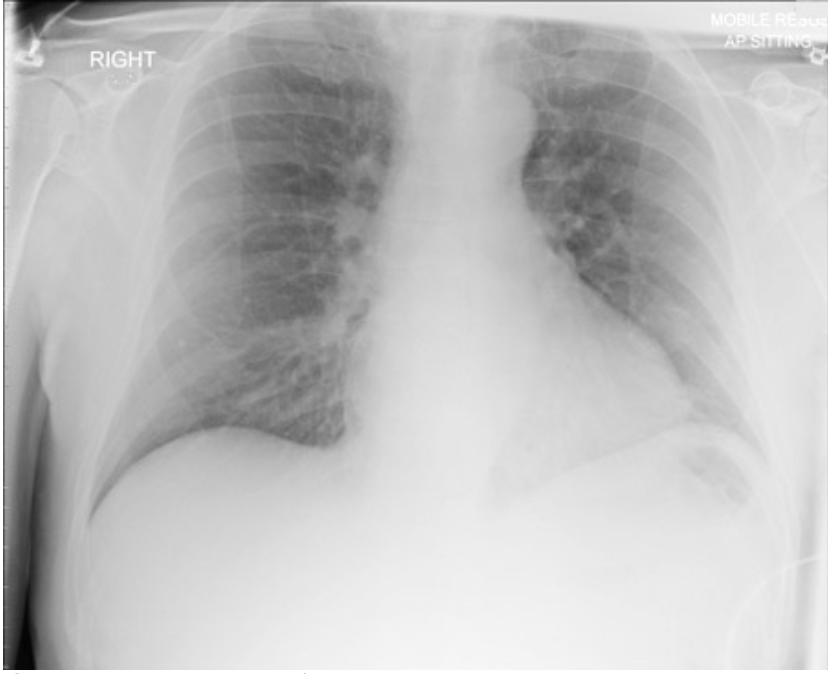

1

AP or PA

AP = scapula further medial